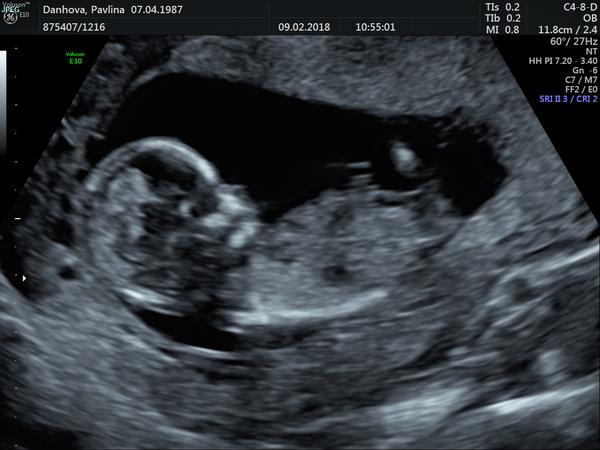

Pohlaví dle ultrazvuku

:o) Takhle nějak vypadal ten náš malej 🙂) Ale nevím no. Spíš než na obrázek bych dala na to, co cítíš ty sama, já to třeba poznala hned už v 7 týdnu a nemýlila jsem se.

@miaelle90 myslím si, že holka. Pohlavni hrbolek moc není vidět, ale bylo mi vysvětleno, že pokud je vodorovně s páteří, je to holka. Pokud je maličko vychýlený, tak chlapeček. Sedělo mi to u obou dcer.